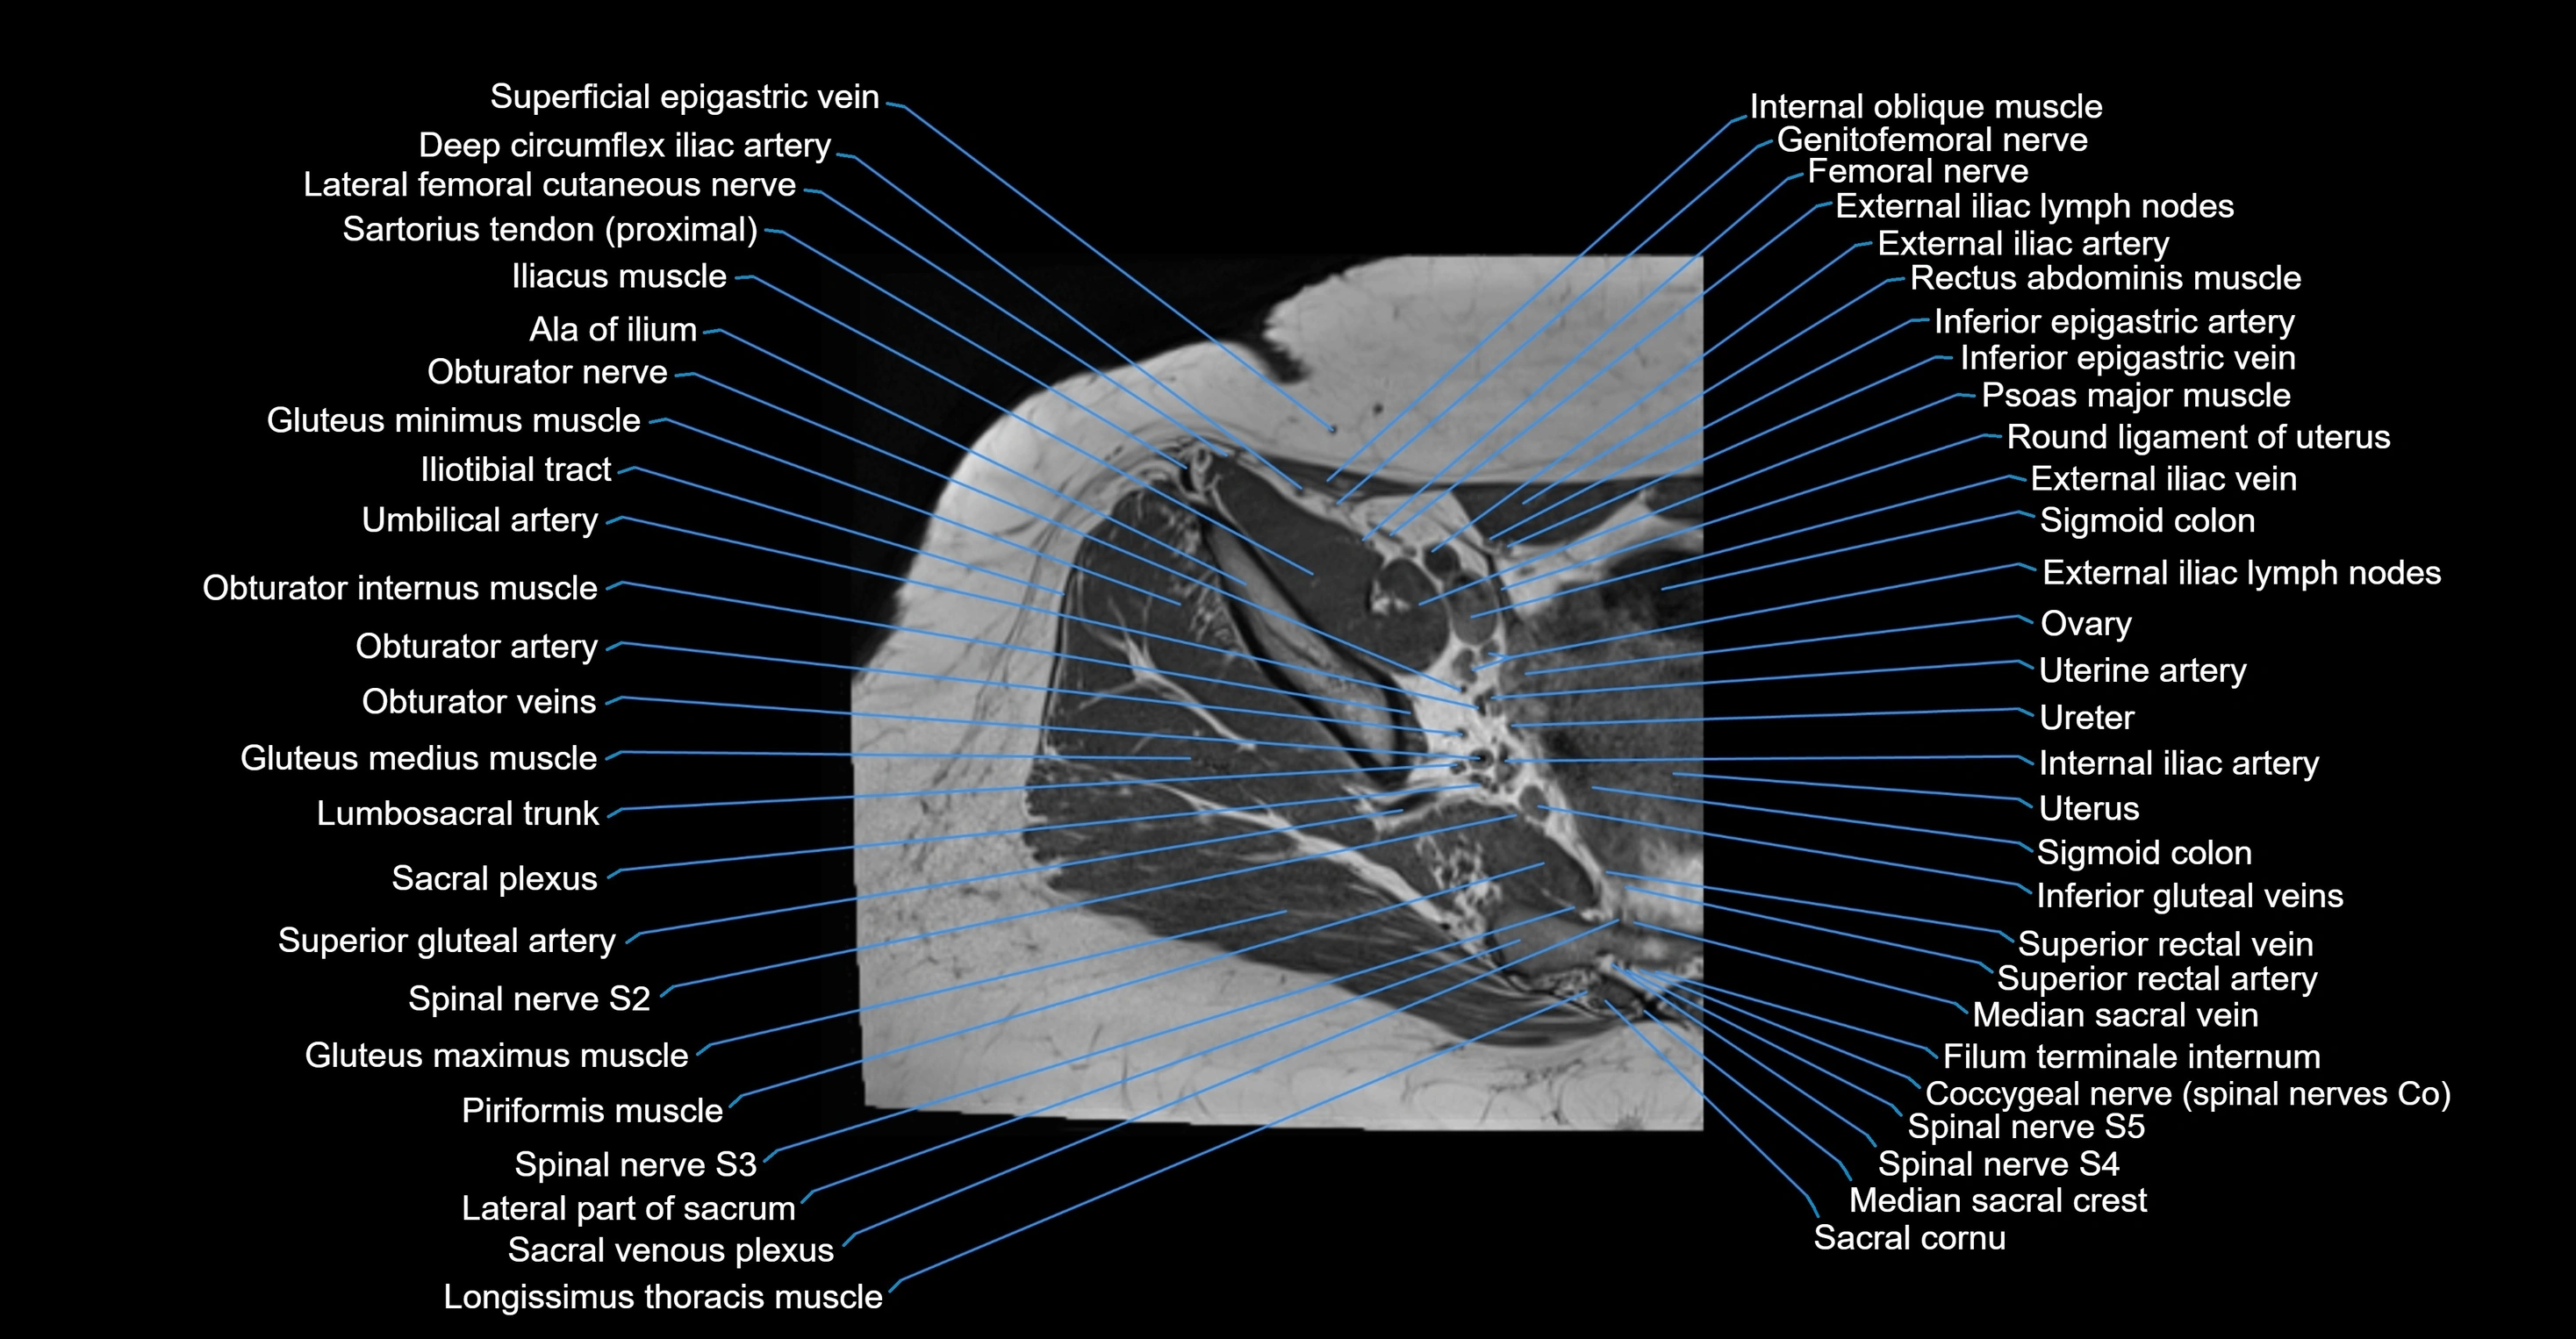

- Deep circumflex iliac artery

- External iliac artery

- External iliac lymph nodes

- External iliac vein

- Femoral nerve

- Genitofemoral nerve

- Gluteus minimus tendon

- Inferior epigastric artery

- Inferior epigastric veins

- Internal iliac artery

- Lateral femoral cutaneous nerve

- Lumbosacral trunk

- Median sacral vein

- Obturator internus muscle

- Psoas major muscle

- Round ligament of uterus

- Sacral plexus

- Sigmoid colon

- Spinal nerve S2

- Spinal nerve S3

- Spinal nerve S4

- Spinal nerve S5

- Superior gluteal artery

- Superior rectal vein

- Tensor fasciae latae muscle

- Umbilical artery

- Uterine artery

- Uterus